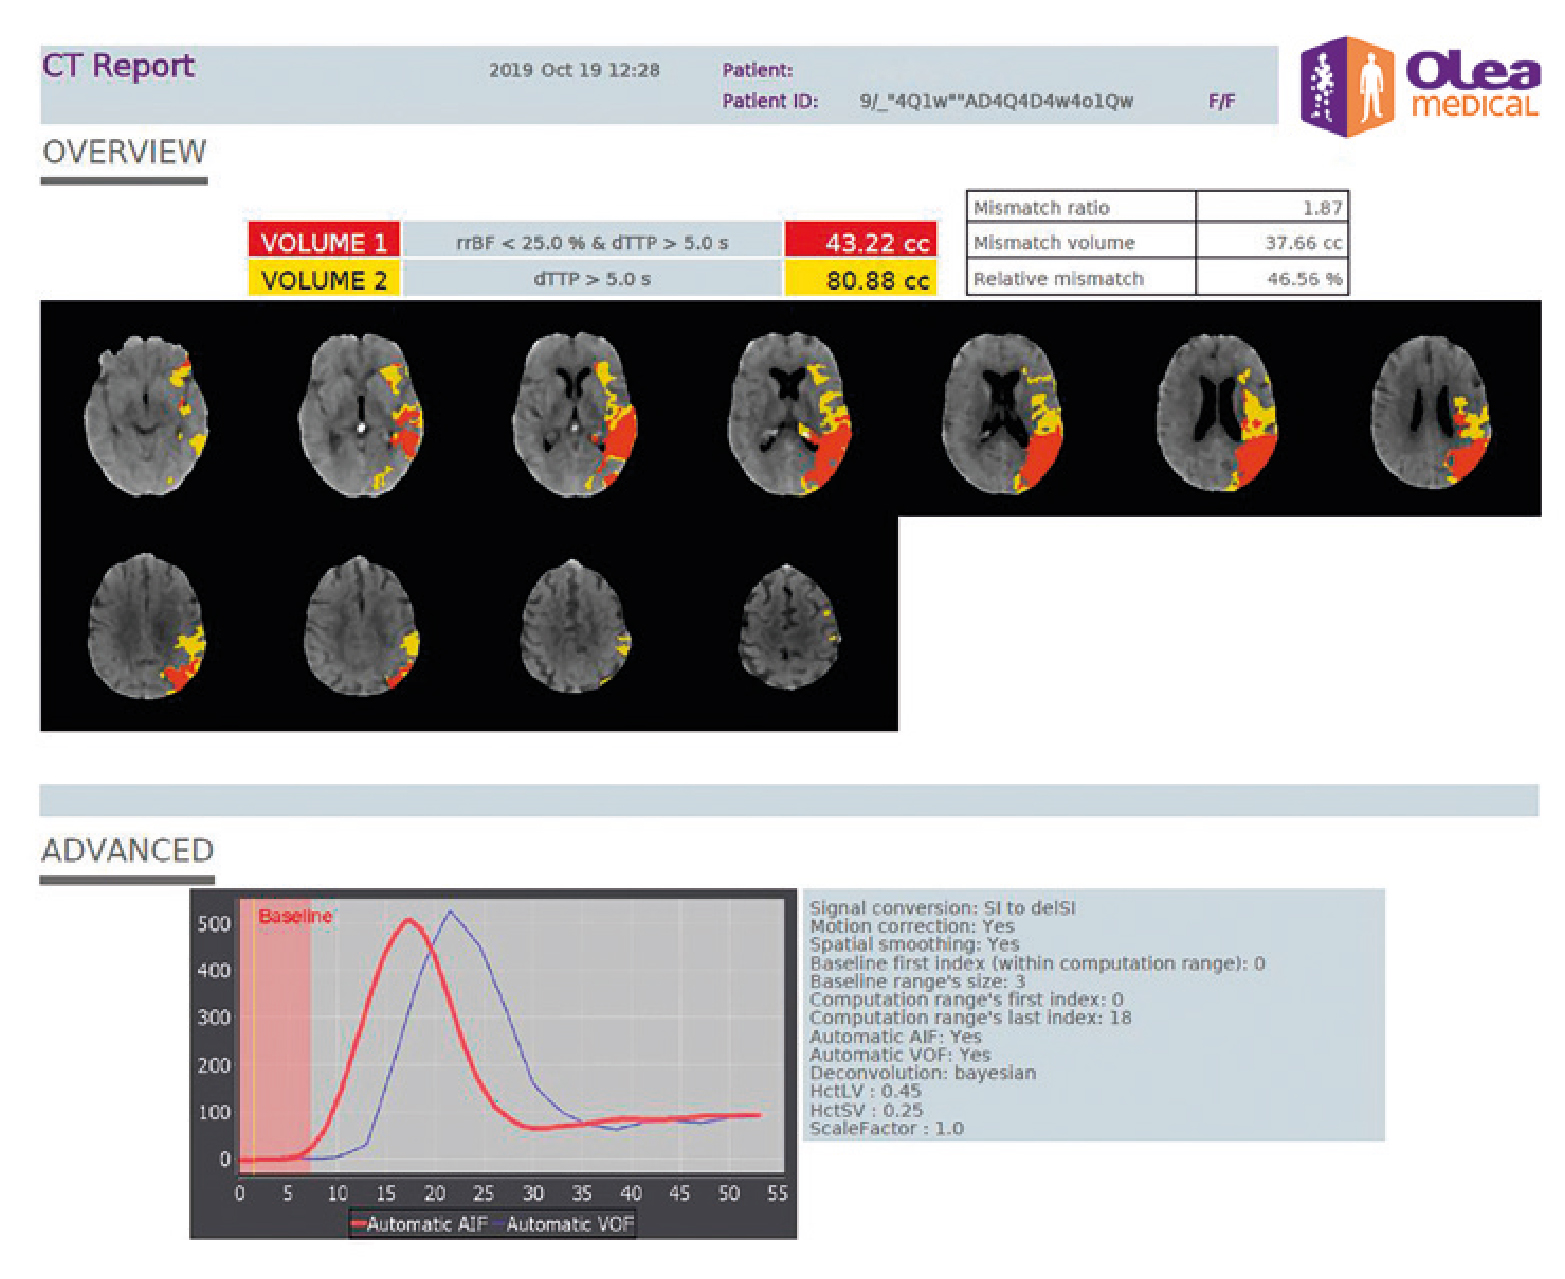

- Решение для мгновенного инсульта для МРТ с автоматическим составлением отчетов

Мгновенный и стандартизированный отчет об инсульте с автоматическим вычислением несоответствия